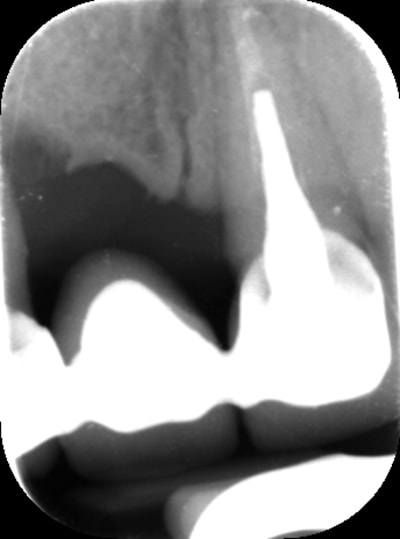

Bon voila le scann de 11-12 (pas 21-22 comme noté)

C'est vrai que j'ai à mort d'os en épaisseur.

Le manque est surtout en hauteur.

Dans tous les cas je refais 21 en même temps.

j'ai l'impression qu'il ne manque pas d'os en verticale, ou à peine en 12.

Un bon cj avec un lambeau décalé en palatin ou en rouleau pour gagner en épaisseur me semblerai suffisant

le montage guide RX laisse supposer un manque d'un mm en 12 et ok en 11. Surcomble en cj pour en éliminer au cas où avant les empreintes

Bon ben j'ai implanté avant d'avoir refait la 21. Du coup j'ai mésialé la pose de 11 pour compenser la distalisation de 21.

Au final je n'ai pas fait de greffe osseuse... et j'ai réalisé une technique de rouleau sur 11-12 mais je reste un peu court à mon goût.

Une greffe osseuse aurait bcp aider, les implants sont trop enfouis par rapport à la 21.